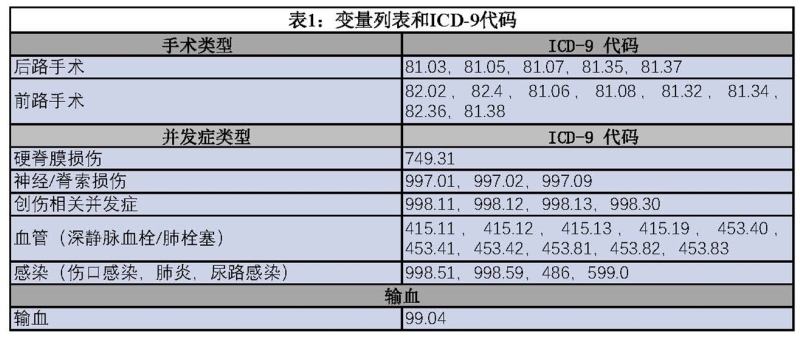

15年期间,共有897例EOIS患者,其中546例(61%)需要手术治疗。EOIS患者的脊柱畸形手术率显著下降(从1997年的75%到2012年的47%),P=0.019(图 1)。

图1 15年研究期内美国EOS手术术式趋势

手术方式上,62%(n=342)的患者行后路手术,13%(n=71)的患者行前路手术,24%(n=133)的患者行前后路联合手术。后路手术从1997年的33%显著增加到2012年的91%,(P<0.004)。前后路联合手术从50%降至4.3%(P<0.001)。前路手术也从17%降到4.3%,(P<0.126),但此无统计学意义。